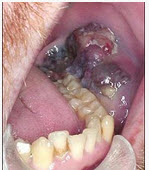

男性患者,50岁,发现口内粘膜黑色肿物两年,近期生长迅速,且破溃,出血,伴疼痛,有颌下淋巴肿大。如图:

。最可能的诊断为()

A.海绵状血管瘤

B.复发性溃疡

C.舌下腺囊肿

D.恶性黑色素瘤

E.颊粘膜癌